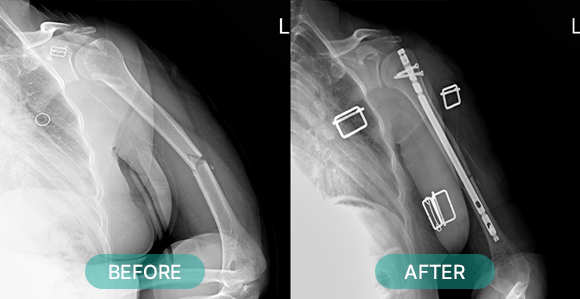

관혈적 정복이란 골절된 부위를 절개하고 뼈를 노출시켜 눈으로 직접 보면서 골절편을 정확하게 맞추는 방법으로 금속판과 나사 고정법, 핀고정법, 나사고정법, 골수 내정 고정법, 인공 관절 치환술, 외고정 기구 고정법 등등 여러 방식이 있습니다.